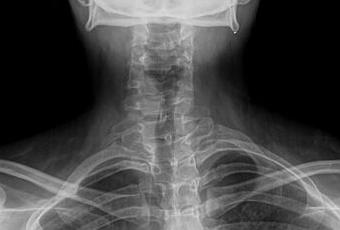

RADIOGRAFIA AP Y LATERAL DE COLUMNA CERVICAL

-Cuerpos vertebrales, con leve angulación hacia derecha. Existe desplazamiento anterior de C3 y C4, menor 25%. Lordosis cervical, rectificada.

-Cuerpos vertebrales con altura preservada, sin evidencia de lesiones líticas, blásticas o perdida de la contigüidad. Con presencia de algunos osteofitos marginales en C5.

-Espacios intervertebrales, con disminución de su amplitud a nivel de C5-C6 y C6-C7.

-Neuro forámenes, con disminución de su amplitud a nivel de C5-C6 y C6-C7.

-Espacio entre apófisis odontoides y C1, menor de 3 mm.

-En topografía de epiglotis se observa trazo horizontal radiopaco que podría corresponder a restos alimenticios óseos.

ASIMETRÍA ESPINAL DEXTROCONVEXA Y RECTIFICACIÓN DE LORDOSIS CERVICAL.

ANTEROLISTESIS DE C3 Y C4, GRADO I DE MAYERDING.

DISCARTROSIS A NIVEL DE C5-C6 Y C6-C7, ASÍ COMO ESTENOSIS DE NEURO FORÁMENES.